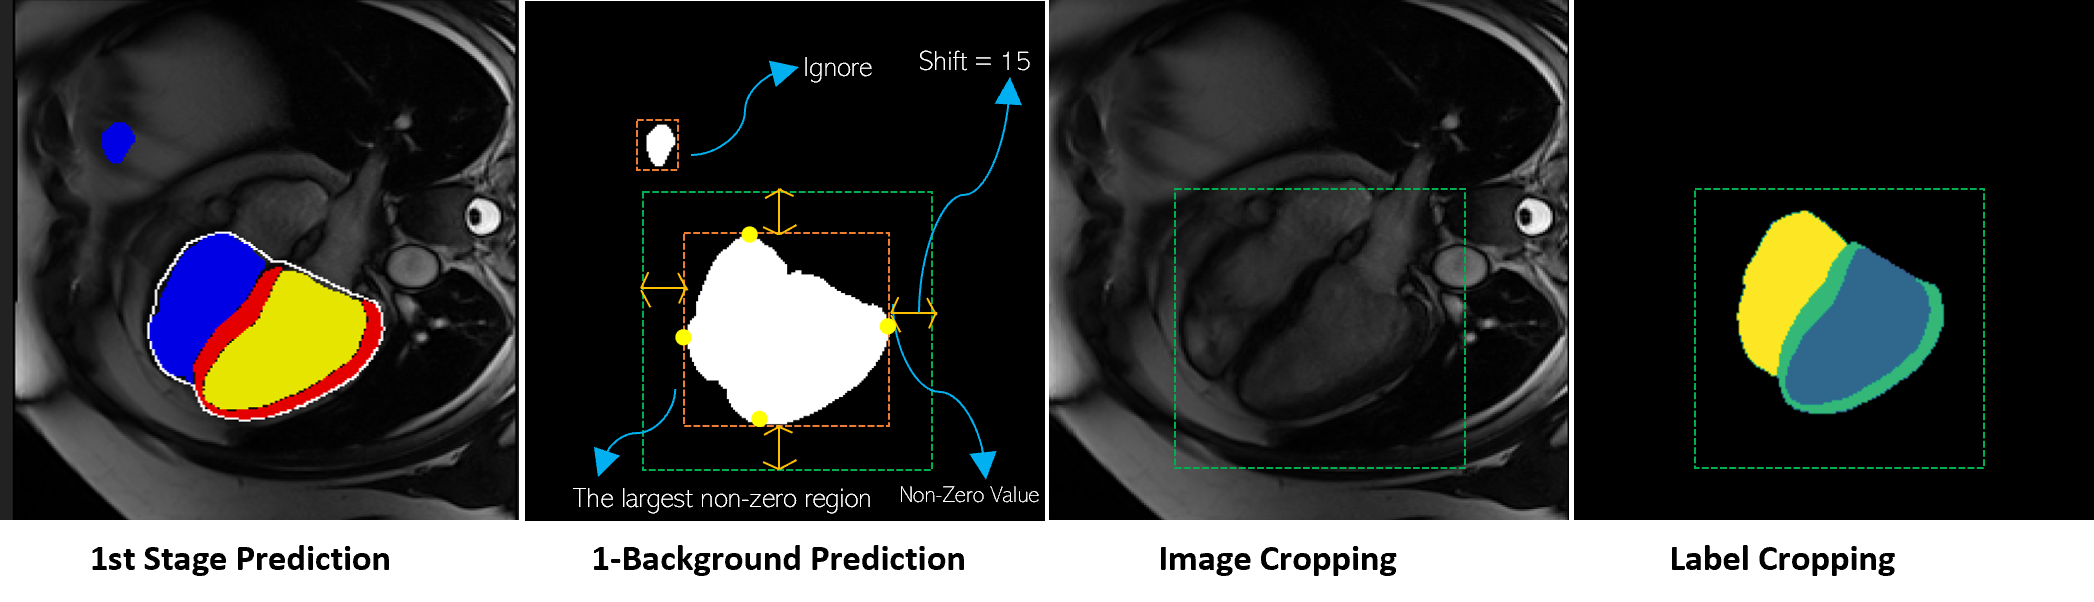

Cropping: The prediction generated in the first stage utilizes a full-size image, potentially leading to outliers or errors, as illustrated in Fig. 2. To address this, we employ background predictions to identify and remove such outliers. The heart region is extracted from both the intensity image and ground truth. The detection is performed by identifying the largest connected region from element-wise negation of the background predictions. To ensure a safety margin that encompasses the entire heart, the bounding box is expanded by ’shift’ of 15 pixels.

Specialist Networks: The specialist networks, lightweight encoder-decoder networks with a similar architecture to E-2AUNet, have three instances (LV-Net, RV-Net, and MYO-Net) with a weight-sharing strategy and cross-efficient additive attention blocks (cross-E-2A), in the encoders. The specialist networks work only on the cropped heart regions, having a smaller size compared to the original size image. The baseline feature maps start at C1:16 and grow as C2:32 C3:64 C4:128 C4:256. Additionally, the specialist networks share weights at all stages of the encoder-decoder. Interactions between features from the three encoders occur through the cross E-2A block. This cross-attention mechanism serves as a soft relative shape prior, aiding the network in rectifying geometric shapes in different areas of interest and thereby contributing to a more precise segmentation, as discussed in the ablation study.